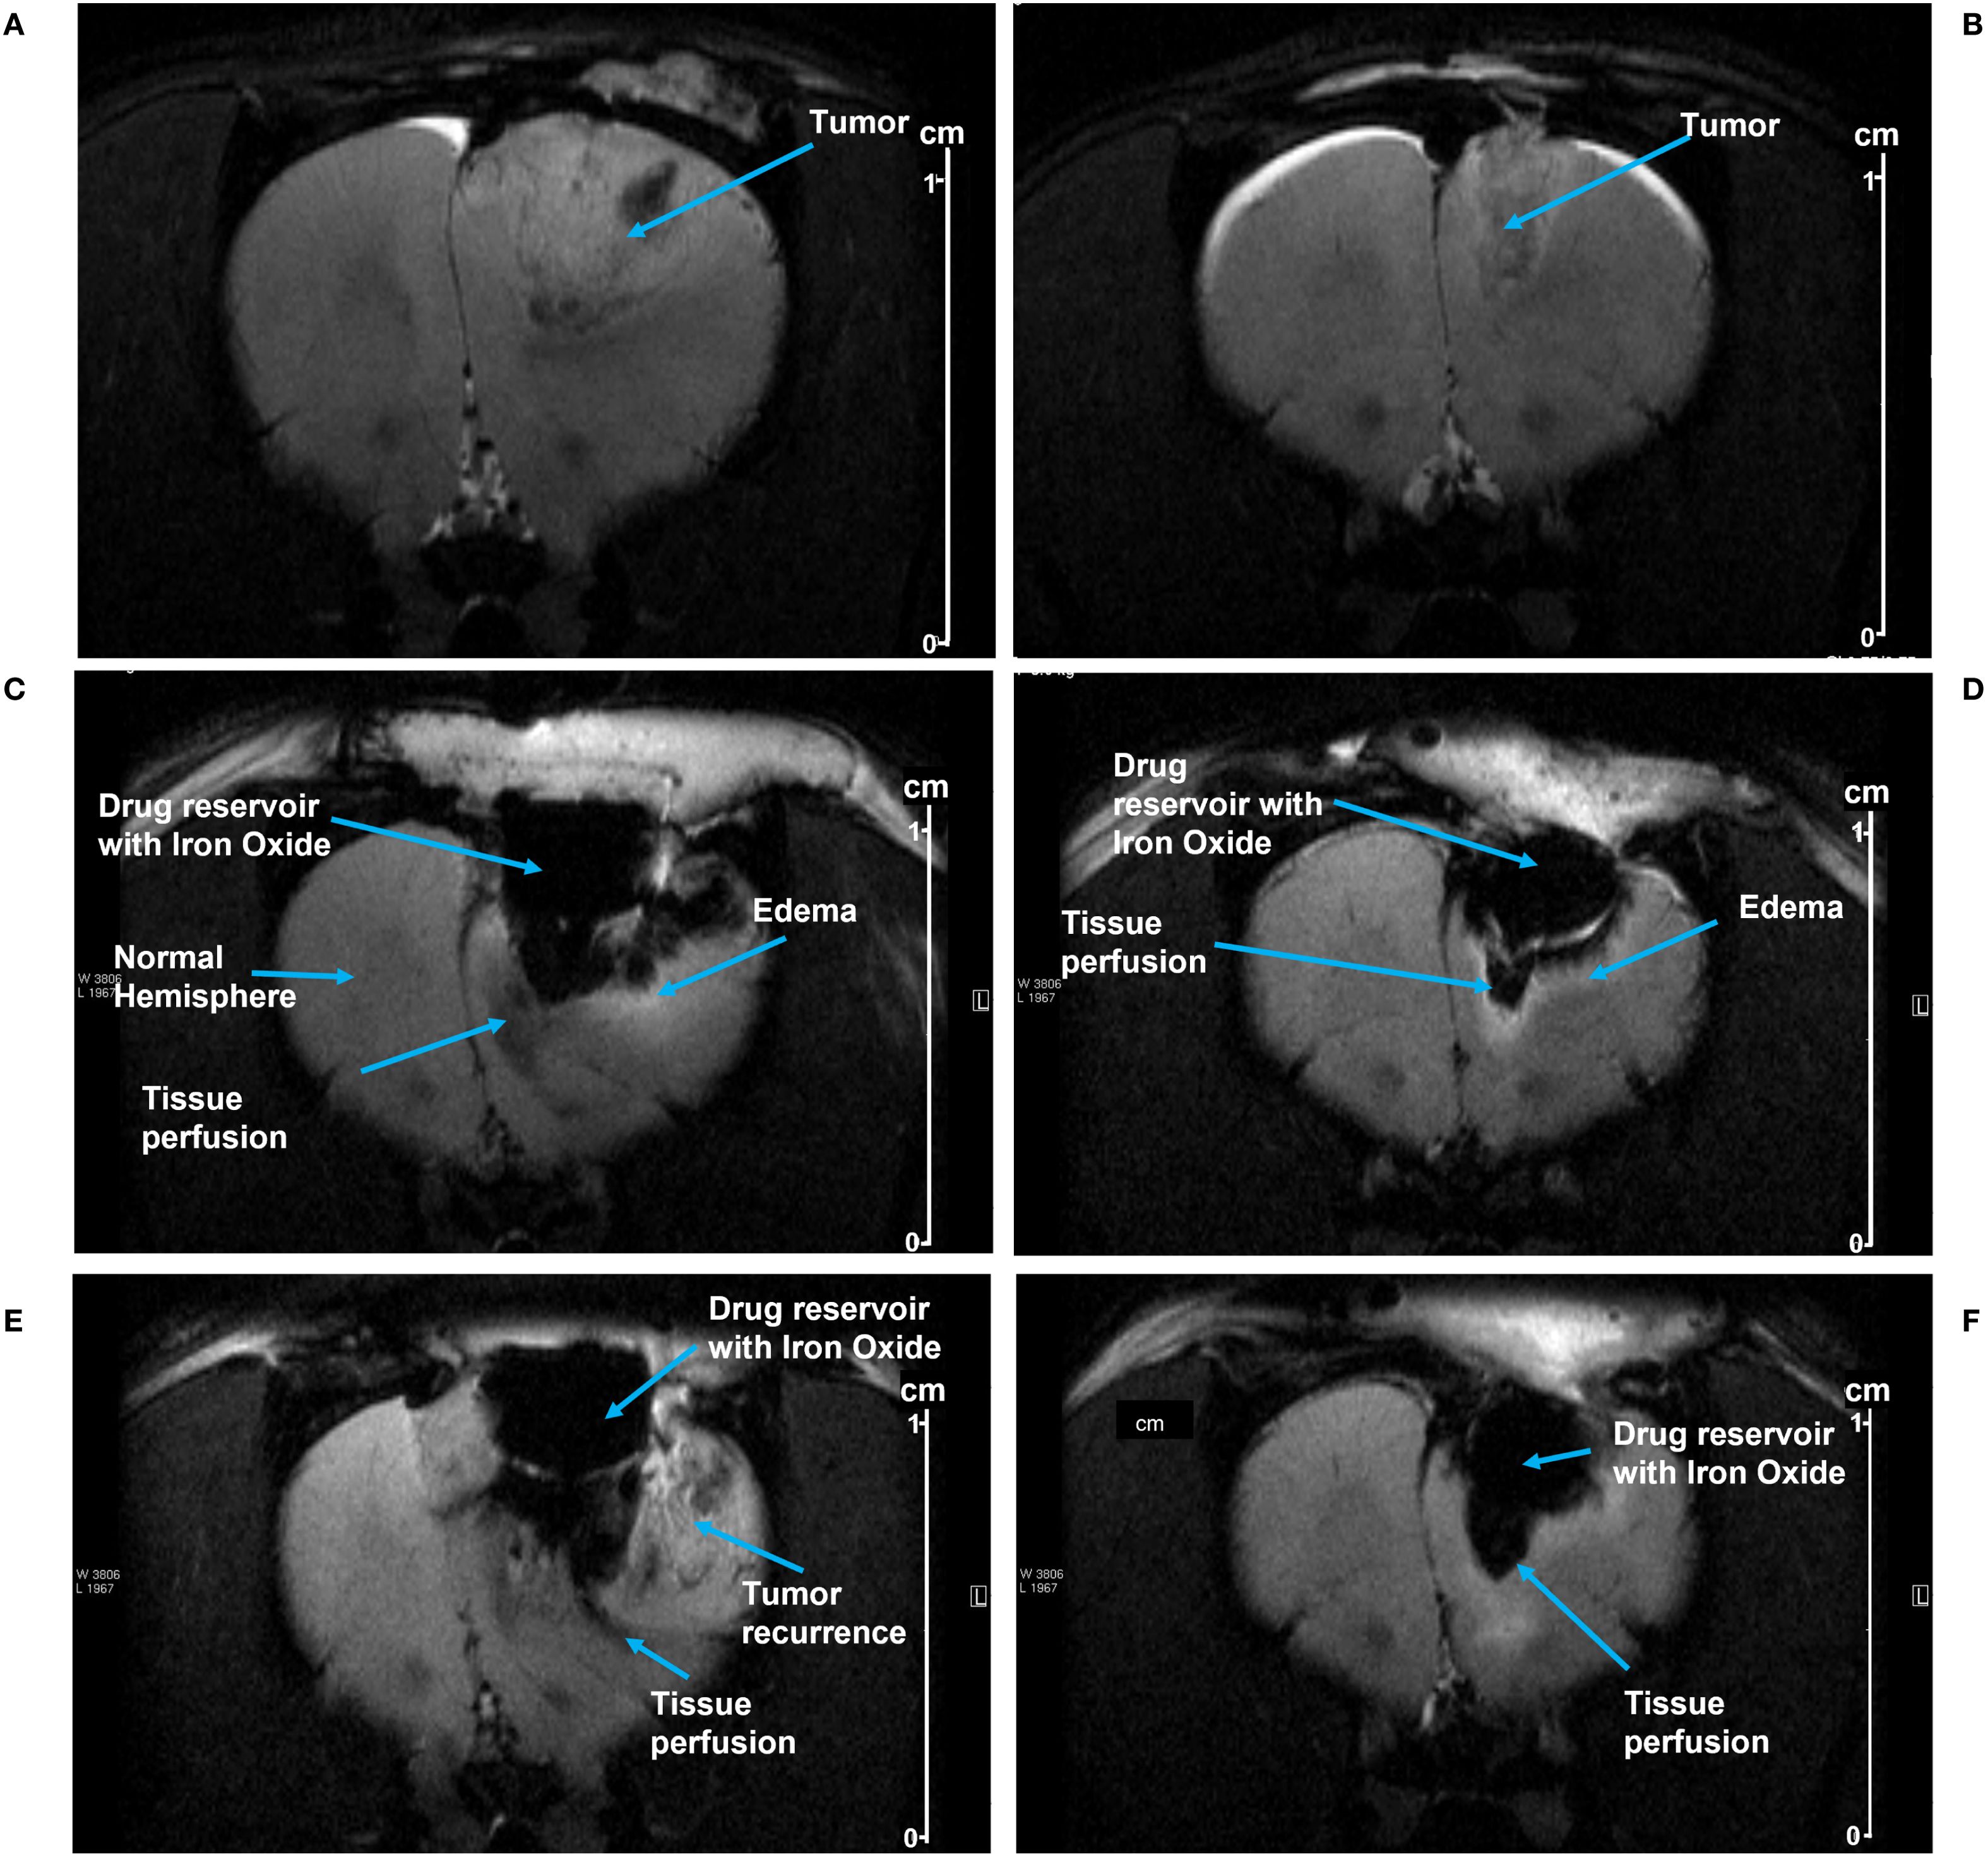

A rat C6 glioma model was used to evaluate pump function in vivo. Growth of the tumor was monitored by MRI. Figures 4A, B depict tumor growth in two animals, Rat 1 and 2, respectively; Rat 1 was imaged on Day 12 post-injection, and Rat 2 was imaged on Day 13 post-injection. Tumors were resected from both rats and pumps implanted on Day 14 post-injection; two weeks of tumor growth provided a resection cavity of sufficient size to implant a pump.

Figure 4. (A, B) show MRI images of tumor growth prior to resection in Rat 1 and Rat 2, respectively. After pump implantation, MRI images show SPION perfusion over time into the tumor resection cavities in Rat 1 at day 5 (C) and at day 8 (E); and in Rat 2 at day 2 (D) and at day 9 (F). The perfusion area was manually delineated beneath the pump, using the distinct contrast between iron oxide and the surrounding tissue (see the methods). Scale shown at right (cm).

MRI images from Rat 1 show pump activity on days 5 and 8 post-implantation (Figures 4C, E respectively). Fluid/SPION is evident in the inferior portion of the pump in both C and E, along with subtle edema. A hyperintense T2 signal was observed in the parenchyma inferior and lateral to the pump chamber, indicating edema and/or fluid related to inflammation and/or tumor recurrence. Beneath the pump in the tissue perfusion zone, T2 hypointensity was noted, representing SPION perfusion and correlating with the signal intensity findings shown in Table 1. Figures 4D, F show MRI images from Rat 2 on post-implantation days 2 and 9, respectively. Again, SPIONs were observed in the inferior and lateral portions of the pump. However, in this rat there was no indication of tumor recurrence and minimal inflammation. A subtle hyperintense T2 signal along the tumor fluid interface is likely attributable to edema/inflammation. Beneath the pump, the T2 hypointensity correlated with SPION perfusion.